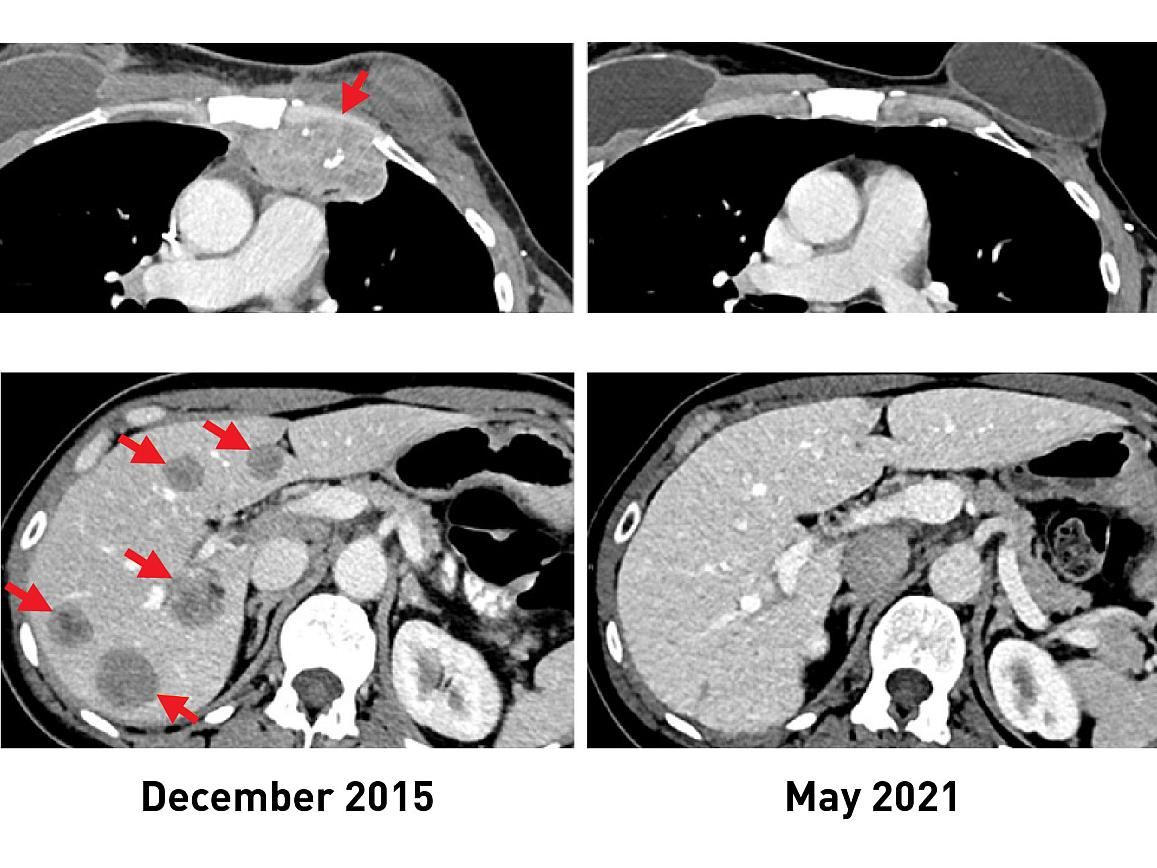

In a clinical trial of 42 women with metastatic breast cancer, 28 (or 67%) generated an immune reaction against their cancer. The approach was used to treat six women, half of whom experienced measurable tumor shrinkage. Results from the trial appeared Feb. 1, 2022, in the Journal of Clinical Oncology.

The results of the new study come from an ongoing phase 2 clinical trial being carried out by Dr. Rosenberg and his colleagues. This trial was designed to see if the immunotherapy approach could lead to tumor regressions in people with metastatic epithelial cancers, including breast cancer. In 2018, the researchers showed that one woman with metastatic breast cancer who was treated in this trial had complete tumor shrinkage, known as a complete response.